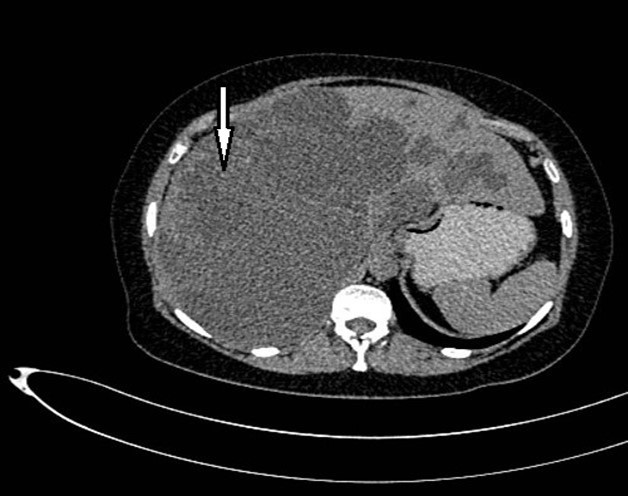

Abdominal tomography reported hepatomegaly secondary to polycystic disease and was reported with 3 cysts of greater size of 17, 14 and 12 cm in approximate diameter (Figure 1, Figure 2), kidney transplant without problems; the liver with mass effect on the stomach, the vena cava partially occluded, uncomplicated colon diverticulosis. Laboratory creatinine 1.44mg/dl urea 51.9 md/dl, glucose 71mg/dl, normal liver function tests.

Figure 1.Non-contrast CT shows hepatomegaly by multiple clusters of cysts.